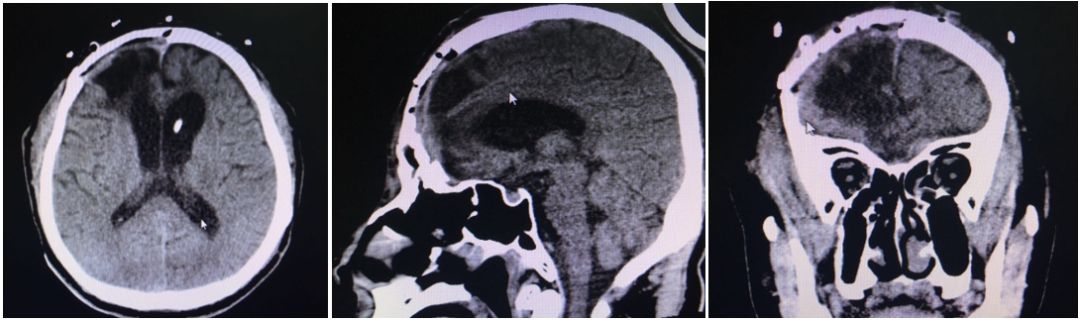

迈普神外之声丨peek材料在颅骨的精准修复